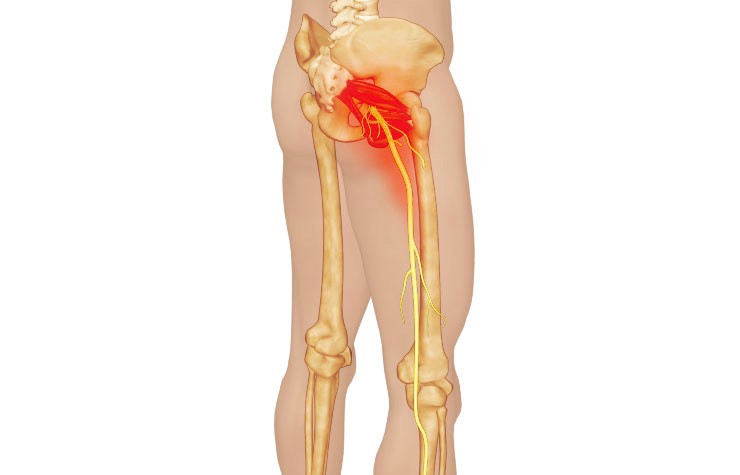

6. 신경학적 원인

골반 신경에 영향을 미치는 신경학적 장애는 만성 골반 통증을 유발할 수 있습니다. 골반 신경통, 신경 포획 증후군과 같은 질환은 지속적인 불편함을 유발할 수 있습니다.

이러한 질환은 신경 손상이나 압박을 수반하여 골반 부위에 통증 신호를 전달됩니다.